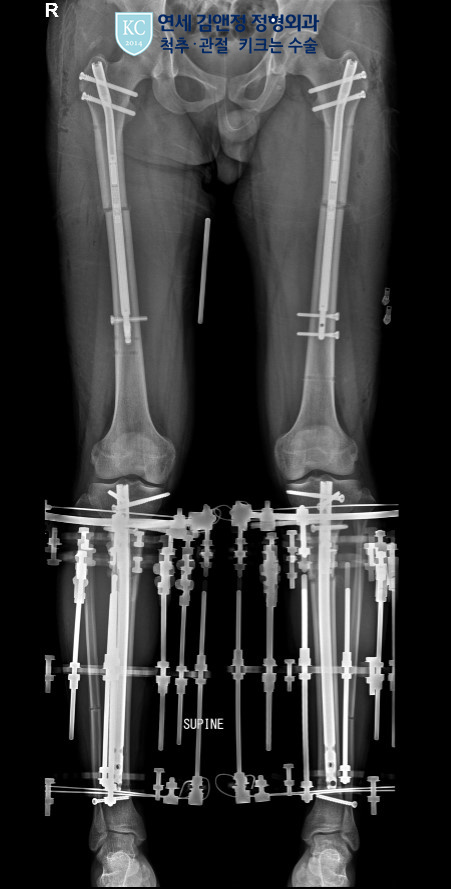

하지 연장술에서 동시 연장은 키 수술 연장 기간을 줄이면서 더 많은 키 연장을 할 수 있는 수술이다. 키 수술에서 허벅지 연장의 특징인 연장 중에 골진 형성이 충분한 장점을 이용해서 종아리와 허벅지를 약간의 시간차를 두고 수술 후 허벅지 길이를 연장하는 기간을 종아리를 연장 후 기다리는 굳히기 기간 동안 허벅지를 좀 더 늘리면서 하지연장술에서 가장 지루한 이 연장과 재활 기간을 줄이면서 많은 키 연장을 목표로 하는 키 수술 연장 방법이면서 최신 유행 트렌드이다.

입원 -> 다음날 1차 수술( 종아리 수술부터, 종아리 속성 연장 또는 종아리 프리사이스)-> 종아리 수술 1주 후 허벅지 프리사이스수술 -> 다음날부터 종아리 연장 시작 하루 1미리 -> 허벅지 수술 후 5일차부터 허벅지 연장 시작(하루 1미리) -> 종아리 연장 시작 2.5개월 후 종아리 속성 연장 2차 수술(외고정 제거), 종아리 연장 길이 4.5-5센티 -> 이후 약 1개월간 허벅지 연장( 종아리 연장 종료 후 굳히기 기간) 지속 -> 첫번째 수술 후 약 4-5개월 보행 시작.

한 부위에 연장 길이에 무리한 욕심을 자제하고, 종아리와 허벅지를 적절히 연장하면, 종아리 연장 길이를 많이 줄일 수 있고, 까치발 발생을 최소화하면서 허벅지 연장의 장점을 최대한 살리는 이 동시 연장은 일상으로의 복귀를 지연시키는 종아리 한 부위 연장을 많이 하면서 겪게 되는 많은 재활에 걸림돌들을 피하게 되고 이를 통해서 더 많은 연장과 균형 있는 연장 그리고 지루한 연장 기간 또한 줄일 수 있다.